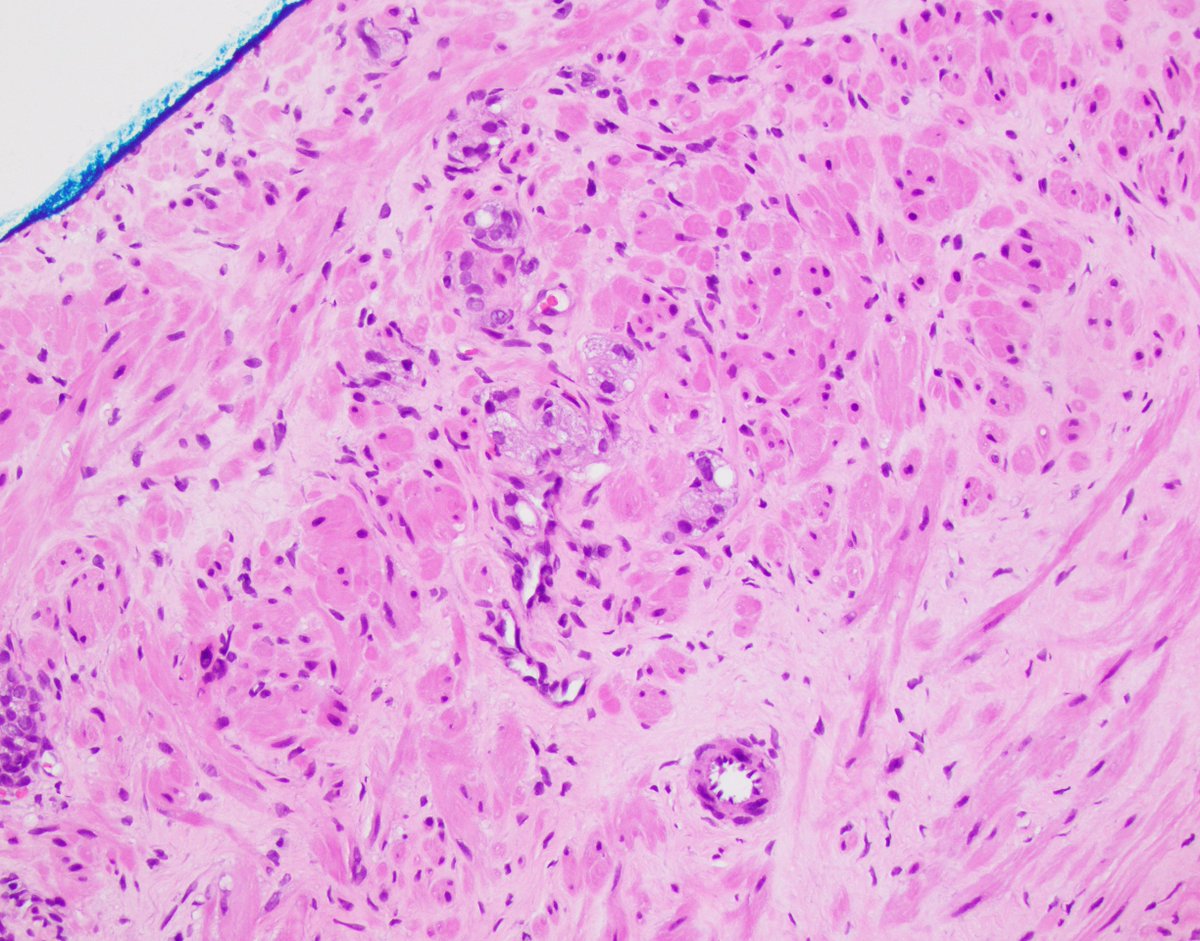

Coarse eosinophilic granules (so-called 'Paneth-like') can be seen in all grades of #prostatecancer #gupath Unlike true Paneth cells [GI tract], these cells are neuroendocrine marker (+), do NOT contain lysozyme